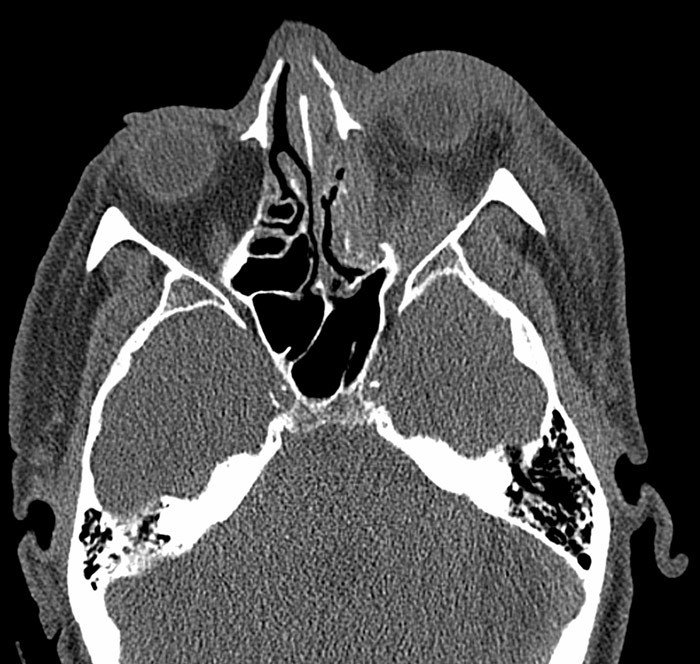

A man in his 60s was hospitalised after sustaining facial trauma in a fall. CT of the face showed nasal fracture, left-sided fracture of the orbital floor and medial orbital wall with dislocation and intraorbital haematoma. The globe was intact (pictured left). Clinical examination revealed left periorbital haematoma and pronounced proptosis. Upon palpation the left eye was tense and inelastic. There was greatly restricted movement of the left eye in all directions, almost to the point of ophthalmoplegia. Direct and indirect light reflexes were absent and there was complete loss of vision in the left eye. Intraocular pressure in the left eye was measured at 70 mm Hg.

Our patient fulfilled all the criteria for traumatic retrobulbar haemorrhage. Four hours after admission, decompression was performed by lateral canthotomy and cantholysis under local anaesthesia (opening of the lateral canthus and transection of the lateral cathal ligament) (pictured right). After the operation the proptosis quickly resolved and after 15 minutes intraocular pressure was 20 mm Hg. Unfortunately, the patient’s vision did not improve in this case. Traumatic optic neuropathy is therefore considered a possible additional diagnosis.